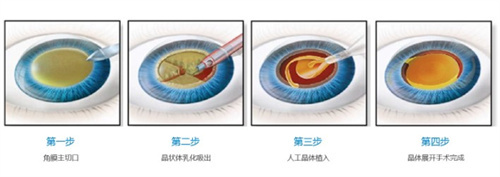

普瑞眼科在济南的口碑一直不错,尤其是其引进的德国蔡司三焦点晶体技术,能帮助老年人一次性解决白内障和老花眼问题。

三焦点晶体:相比传统单焦点,可同时优化远、中、近视力,术后不用戴老花镜。

个性化方案:根据患者角膜状况、用眼习惯定制手术,比如喜欢看书或开车的老人,医生会调整晶体参数优化视觉结果。